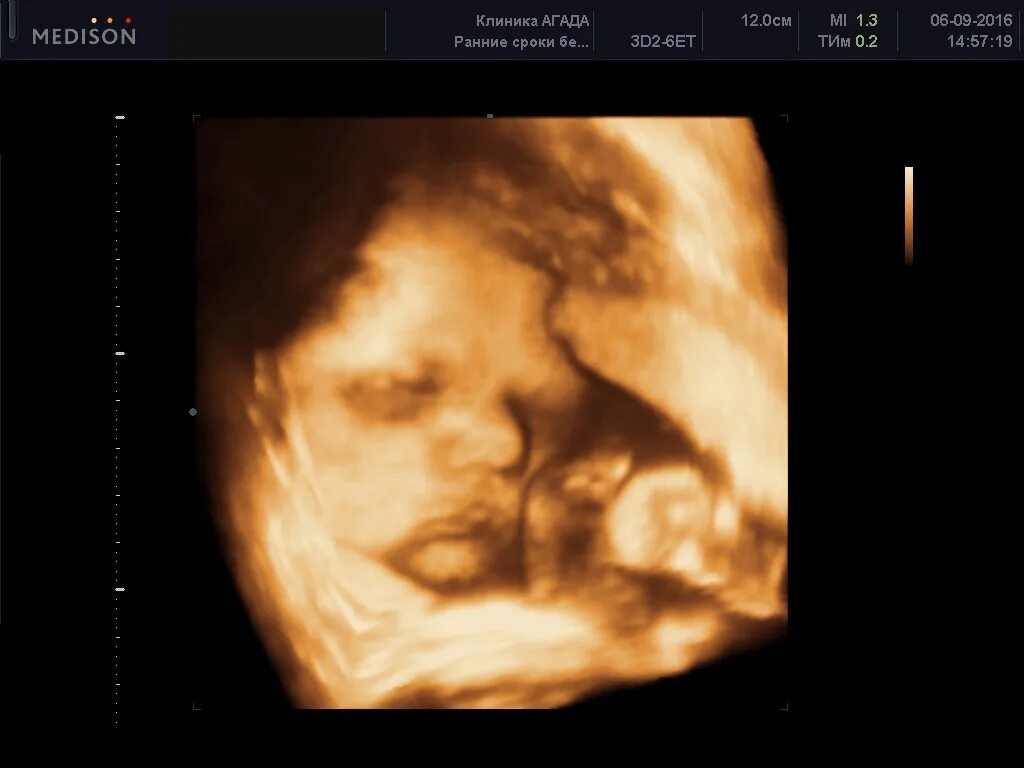

На каком сроке делать 3д